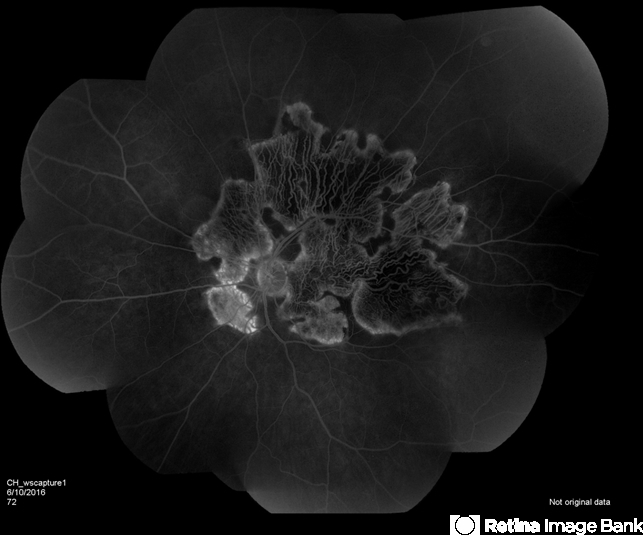

- serpiginous choroiditis

- Fundus camera

- Serpiginous choroiditis.